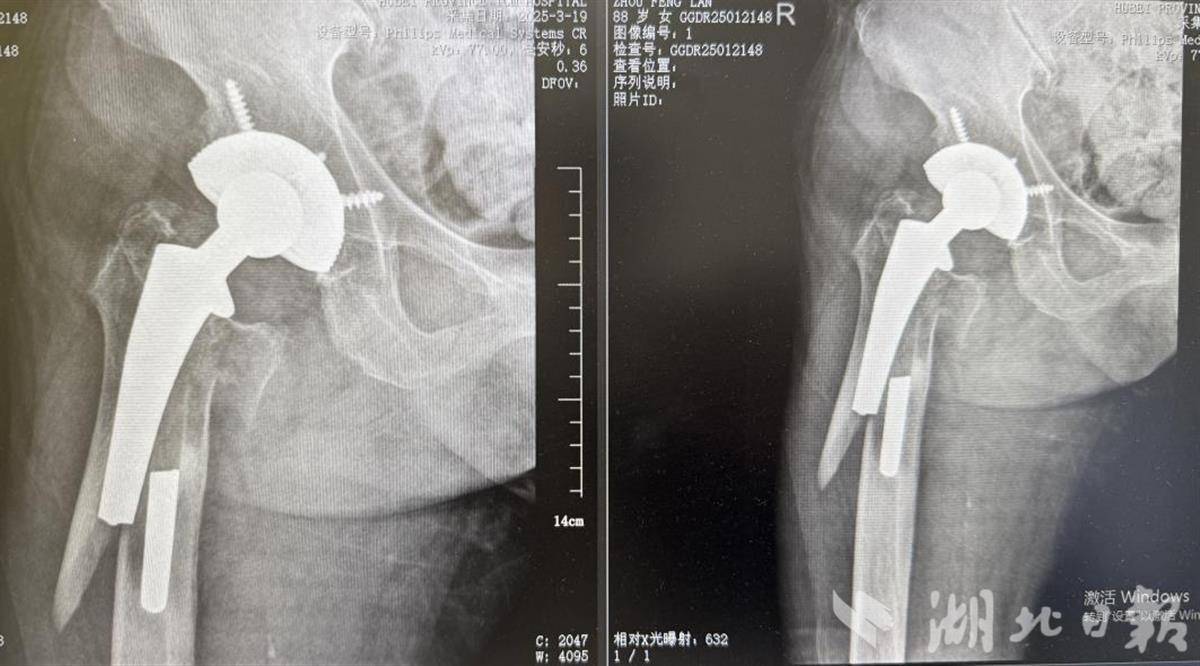

3月17日,周女士在家中不慎摔倒,右髋部剧烈疼痛无法站立,次日前往湖北省中医院(湖北中医药大学附属医院)骨IV科(关节创伤科)就诊。据悉,周女士12年前曾接受过右侧全髋关节置换术,此次摔倒导致股骨假体周围骨折并发生假体断裂。

何伟团队迅速启动多学科会诊,联合麻醉科、心血管病科专家评估手术风险,并制定了个性化的治疗方案。经过术前的身体调理,以及详细的术前沟通和术前准备,3月25日,团队对周女士实施了髋关节翻修及骨折内固定技术,仅用1.5个小时完成了手术,术中出血量少,术后假体位置精准。